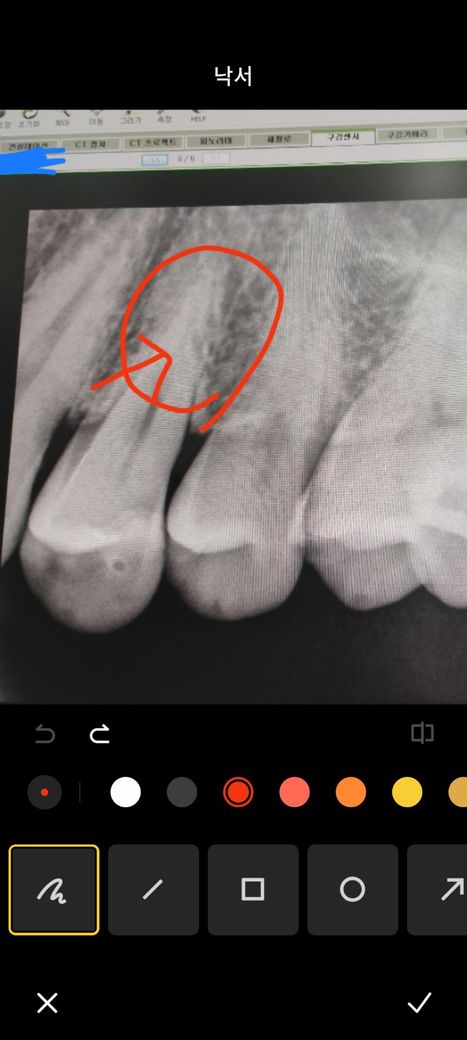

치아 뿌리파절 맞나요? 사진보고 확인부탁드려요

엑스레이 사진상 동그라미친 부분 사선으로 미세하게 뿌리까지

금이 간거 같은데 파절이 맞나요?

2. 엑스레이 사진상 저건 금간게 아니고 신경관이 지나가는 모습입니다

3. 치아가 저런식으로 금이가진 않습니다

4. 신경관이 위에서부터 쭉 이어지지 않는 이유는 부근관때문이거나 석회화 때문입니다